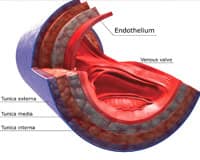

Our inner arterial lining is called the endothelium. It loses youthful function in response to normal aging.

The endothelium is an ultra-thin, one-cell-thick layer of cells that lines your arteries. As you age, your endothelium faces increased vulnerability due to reduced nitric oxide, exposing you to increased cardiovascular disease risk.

Endothelial cells regulate the amount of blood flow through the arterial system.5 With age, the endothelium gradually loses its responsiveness, which leads to a reduction of the amount of blood that flows through the body.6

Researchers use two different, but complementary, methods to discern a person’s risk for cardiovascular disease. Carotid intima-media thickness (CIMT) is a static, long-term measure of arterial thickening (a pathological process) in response to poor endothelial function. Carotid intima-media thickness is a structural measure of how much vascular damage has already arisen from endothelial dysfunction; it is a powerful predictor of future cardiovascular events.36

Another measure of arterial responsiveness is flow-mediated dilation, or FMD. FMD is of growing importance in understanding endothelial function; it measures real-time, dynamic responses of blood vessels to endothelial signal, and has recently been shown to be the best predictor of progressive arterial stiffening, as measured by carotid intima-media thickness (CIMT).18

Think of FMD as the natural complement of carotid intima-media thickness; the former measures minute-by-minute changes in endothelial function, while the latter measures the cumulative effects of years of endothelial dysfunction. Good endothelial defense mechanisms must provide both improvement in FMD (short-term function) to reduce future increases in carotid intima-media thickness (long-term damage). Doing so helps maintain the best possible arterial responses to threats, and optimally lowers cardiovascular risk.